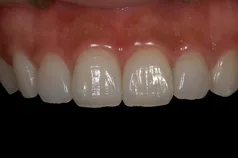

[症例4]

症例3と同様にジルコニア・ブリッジで治療した症例です。

右上中切歯(向かって左上の前歯)が欠損しており、保険のブリッジが入っていました。保険のブリッジは白い部分がレジンという材料でできていますが、経年的に変色するのが大きな欠点です。

治療前は変色があり、歯の長さも不揃いです。

歯の長さがそろうように、歯茎の手術を行い、歯肉がきれいなったあとでジルコニア・ブリッジを装着しています。治療前と比べ、自然で美しい歯になりました。

- 治療期間:6ヶ月

- 治療費:40万円

- 治療回数:18回